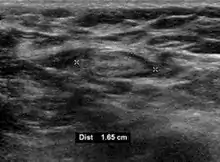

- Absence of the fatty hilum

- Increased focal cortical thickness greater than 3 cm

- Doppler ultrasonography that shows hyperaemic blood flow in the hilum and central cortex and/or abnormal (non-hilar cortical) blood flow.[26]

On ultrasound, B-mode imaging depicts lymph node morphology, whilst power Doppler can assess the vascular pattern.[28] B-mode imaging features that can distinguish metastasis and lymphoma include size, shape, calcification, loss of hilar architecture, as well as intranodal necrosis.[28] Soft tissue edema and nodal matting on B-mode imaging suggests tuberculous cervical lymphadenitis or previous radiation therapy.[28] Serial monitoring of nodal size and vascularity are useful in assessing treatment response.[28]

Lymphadenopathy of more than 1.5–2 cm increases the risk of cancer or granulomatous disease as the cause rather than only inflammation or infection. Still, an increasing size and persistence over time are more indicative of cancer.[39]